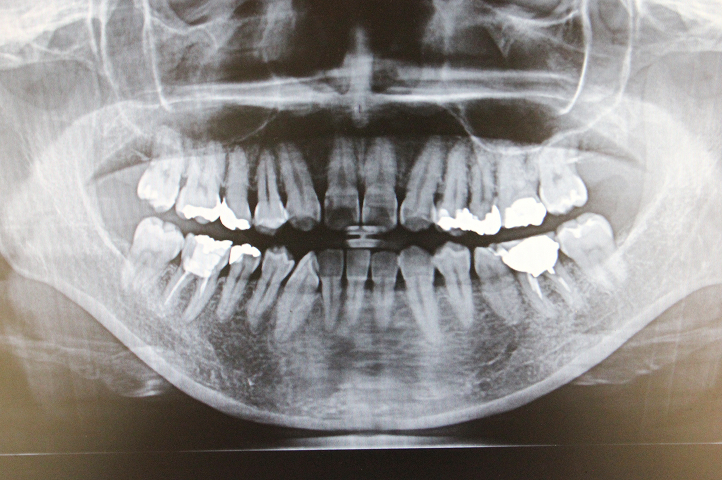

レントゲン撮影

肉眼では見ることができない部分を調べます。

• 歯周病・虫歯の進行度、治療後の歯の状態

• 顎関節の状態

• 埋伏歯(親知らずなど)の状態

クスノセ歯科医院では、日本製CTスキャナー「NAOMI-CT」を使用してレントゲン撮影しています。

被ばく量も少なく、従来のものより撮影できる範囲が広いので、口腔内すべてを一度に撮影できます。